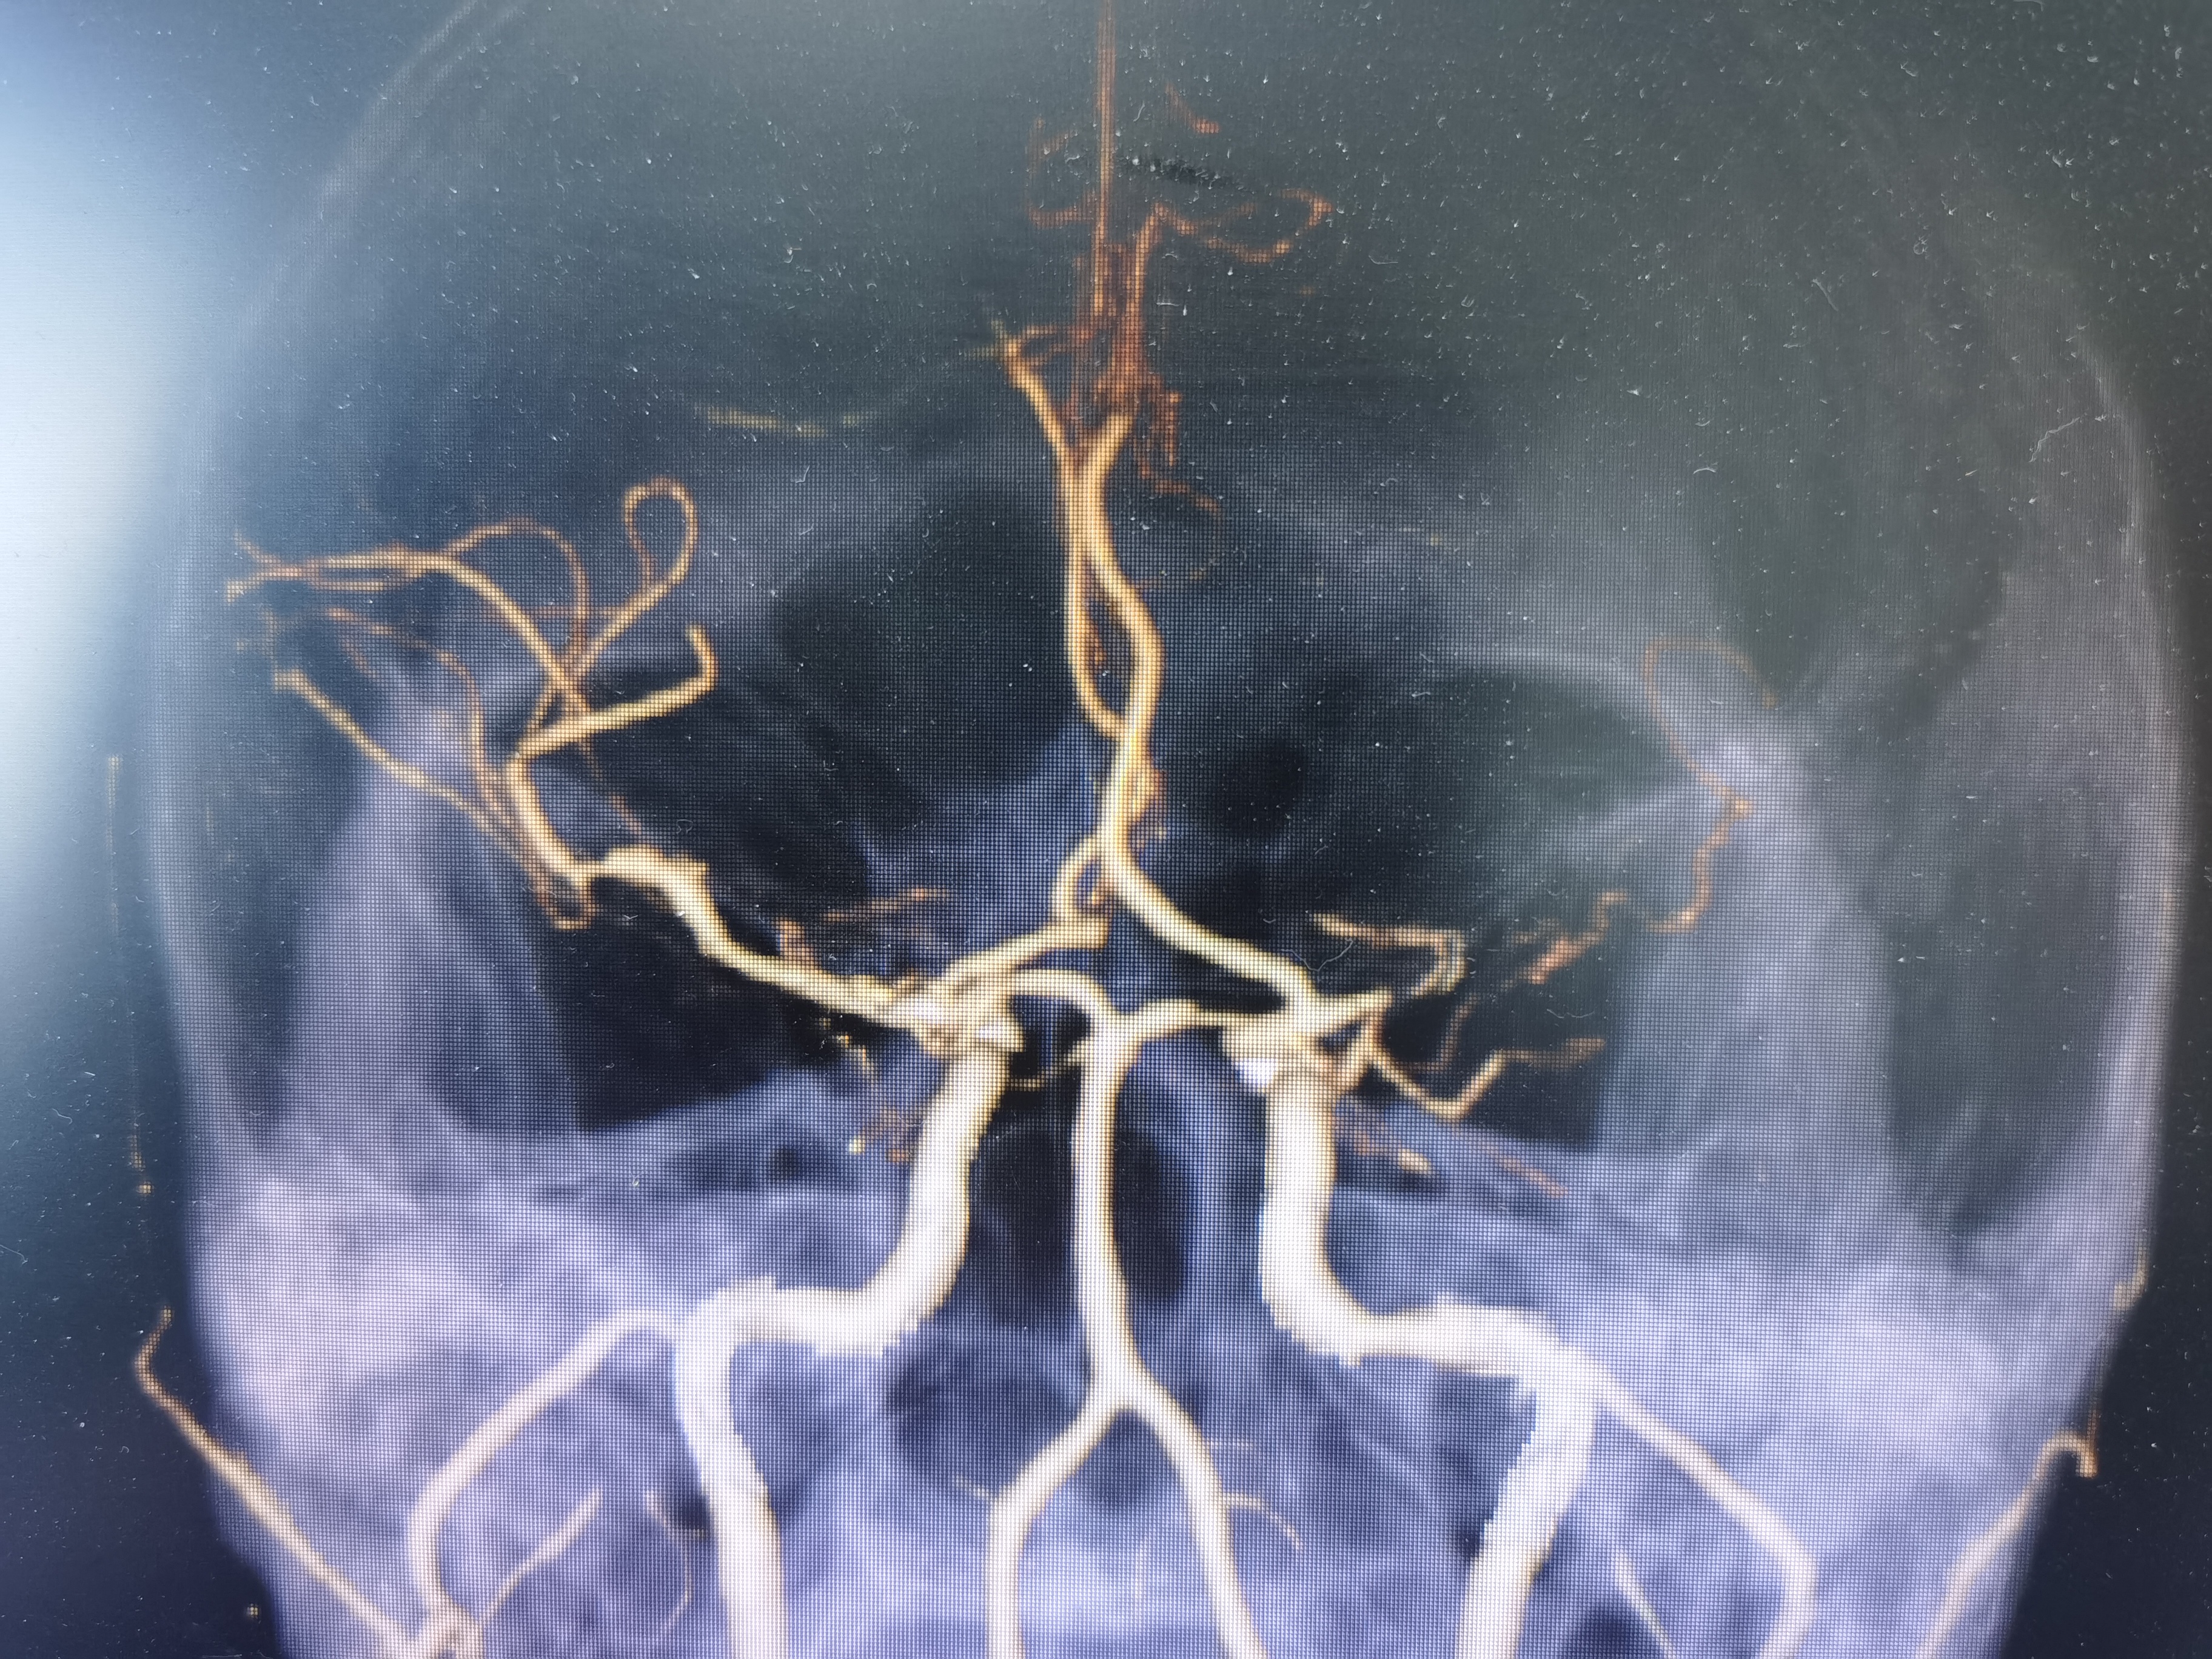

MRA示左侧大脑中动脉M1闭塞。

CTA示左侧大脑中动脉闭塞。

正位见左侧大脑中动脉闭塞。